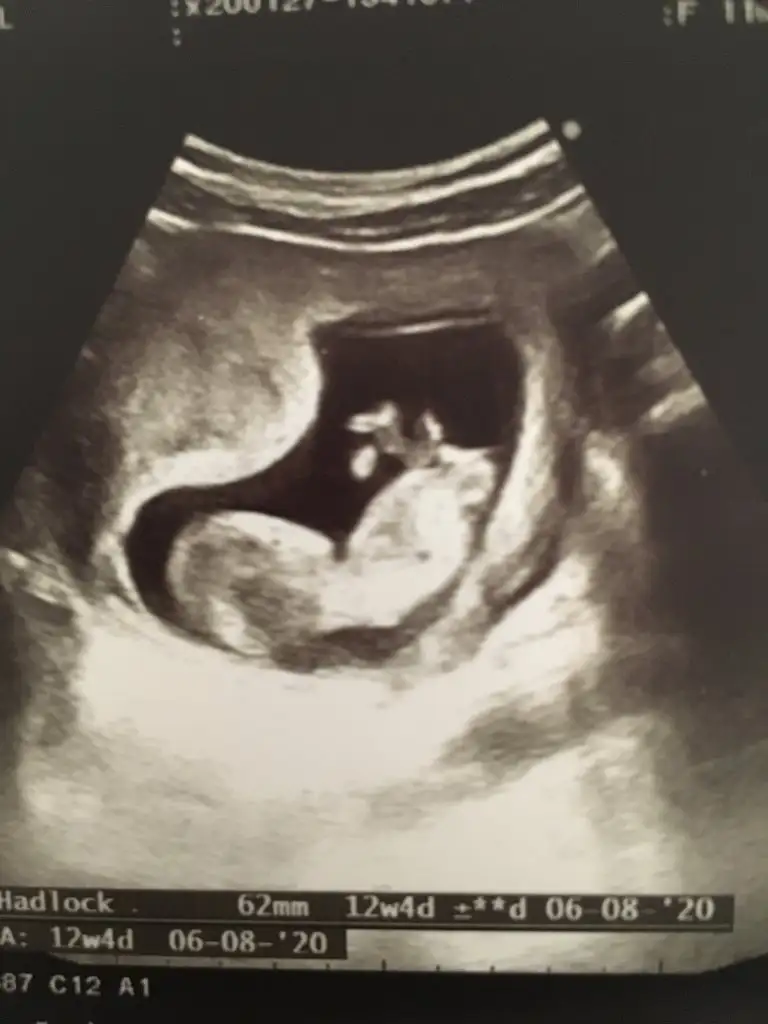

Buda benim bebişim 12 haftalık cinsiyeti sizce nedir😊

45CFB82A-2675-4DCE-89D8-BF5501063824.webp